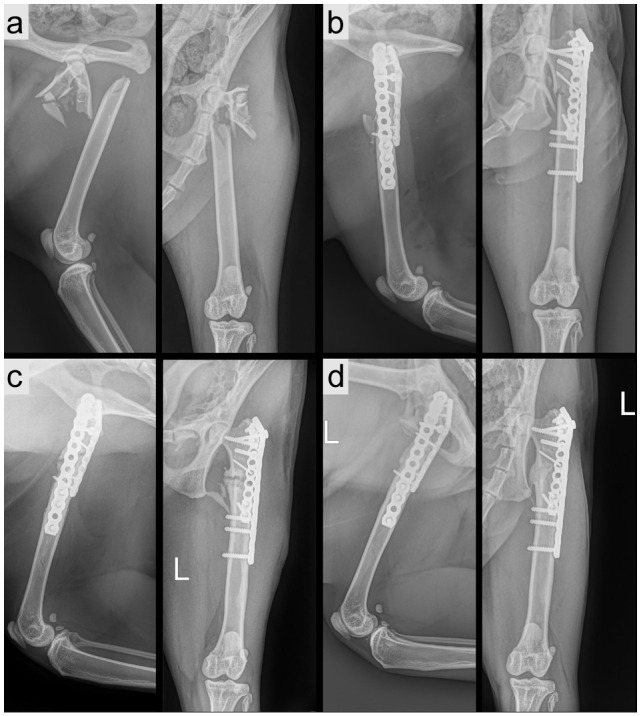

本回顾性病例系列包括四只因股骨近端复杂骨折而接受手术治疗的家猫。回顾了2021年10月至2023年1月期间因高能创伤导致股骨近端粉碎性骨折的猫的医疗记录。所有猫均采用外侧入路进行手术稳定,并完全释放股外侧肌,以改善视野和通路。随访包括物理和影像学评估,并完成猫肌肉骨骼疼痛指数(FMPI)。改良后的入路有助于更好的可视化和植入。平均手术时间76分钟。在随访中观察到3例骨愈合,FMPI评分表明完全恢复。1例需要翻修手术。轻微并发症均得到解决。两只猫后来死于无关的创伤。相关性和新信息股外侧肌的完全释放增加了暴露,促进了猫的复杂股骨近端骨折的成功治疗,没有直接的入路相关并发症。当猫股近端骨折标准暴露不足时,该技术可能是有益的。

Case series summaryFour domestic cats treated surgically for complex fractures of the proximal femur were included in this retrospective case series. Medical records from October 2021 to January 2023 were reviewed for cats presenting with high-energy trauma resulting in comminuted proximal femoral fractures. All cats underwent surgical stabilisation using a lateral approach extended by complete release of the vastus lateralis muscle to improve visualisation and access. Follow-up included physical and radiographic evaluation and completion of the Feline Musculoskeletal Pain Index (FMPI). The modified approach facilitated better visualisation and implant placement. The mean surgical time was 76 mins. Bone healing was observed in three cases with available follow-up, with FMPI scores indicating complete recovery. One case required revision surgery. Minor complications were resolved. Two cats died later from unrelated trauma.Relevance and novel informationComplete release of the vastus lateralis muscle enhanced exposure and facilitated successful treatment of complex proximal femoral fractures in cats without direct approach-related complications. This technique may be beneficial when standard exposure is insufficient in feline proximal femoral fractures.